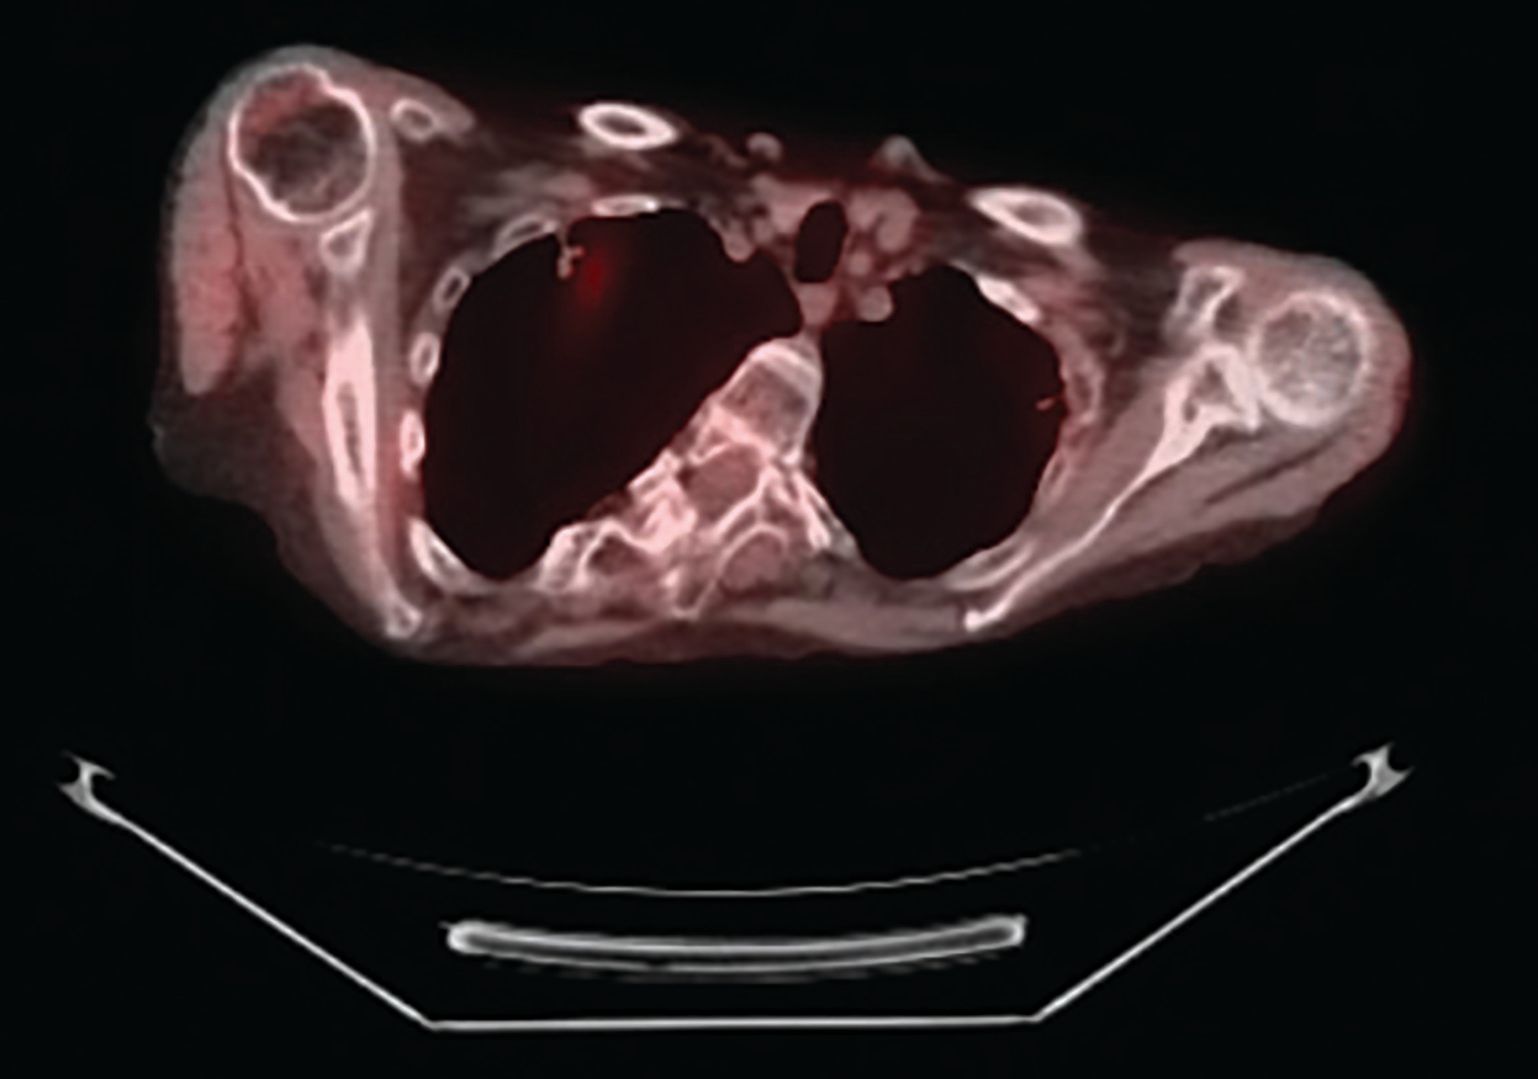

Figure 3. Left Upper Lobe Lobectomy specimen.

A 70-year-old white woman with a 40 pack-year history of smoking has been on follow-up for previously detected abnormal lung nodules during the past 3 years. The most recent computed tomography (CT) scan revealed an increase in the size of the left upper lobe nodule-from 4 mm a year ago to 2 cm on the current CT scan. A CT-guided needle biopsy of this nodule revealed small cell lung carcinoma (Figures 1A and 1B). Further work-up with a positron emission tomography (PET) scan confirmed the left upper lobe lesion with a standard uptake value (SUV) of 12.7, and also revealed a right upper lobe nodule (1.1 cm in size) with an SUV of 2.1 (Figures 2A and 2B). Following multidisciplinary evaluation at the thoracic oncology tumor conference, the patient underwent initial bronchoscopy with ultrasound (endobronchial ultrasound [EBUS]) and biopsy of lymph node levels 10, 7, and 4, followed by a right-sided video-assisted thoracoscopic surgery (VATS) and a wedge resection of the right upper lobe nodule, and a left upper lobe lobectomy (Figure 3). Mediastinal lymph node dissection revealed no lymph node involvement. Pathology of the right upper lobe wedge resection revealed a 1.3-cm non–small cell lung adenocarcinoma, and pathology of the left upper lobe lobectomy revealed a 2.5-cm small cell lung carcinoma (Figures 4A and 4B). Both tumors had visceral pleural involvement and were resected with clear margins. The right upper lobe tumor was staged as pT2N0 and the left upper lobe tumor was staged as pT2N0 (per the 8th edition of the American Joint Committee on Cancer staging system).

Our patient had bilateral upper lobe disease, underwent initial bronchoscopy with ultrasound (EBUS) with biopsy of lymph node levels of 10, 7, and 4, a right-sided VATS wedge resection for adenocarcinoma on the right upper lobe, and a left upper lobe lobectomy for a small cell neuroendocrine tumor on the left side along with mediastinal lymph node dissection. Both tumors had visceral pleural involvement, but they were resected with clear margins. All mediastinal nodes were negative.